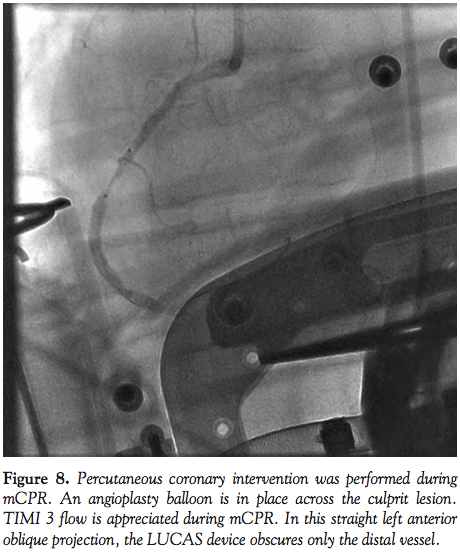

manual CPR and was intubated. Coronary angiography demonstrated a thrombotic culprit mid RCA occlusion (Figure 7). PTCA was performed during continuous mCPR (Figure 8) with subsequent ROSC. A bare-metal stent was placed in the mid RCA with restoration of TIMI 3 flow. An IABP was placed following left coronary angiography and the patient was transferred to the CCU on vasopressors. Despite increasing pressor support, the patient expired 12 hours later with a progressive sepsis-like syndrome.

Fluoroscopic and cineangiographic imaging during mCPR with the LUCAS device requires few significant adjustments. The images presented here represent one center’s experience and diagnostic images were obtained in all cases. Anterior-posterior projections are limited by the height and radio-opacity of the LUCAS drive unit over the patient’s chest. Straight right and left anterior oblique views provide adequate visualization despite the back-brace component of the device being visible on fluoroscopy. As evidenced in Cases 1 and 4, significant cranial angulation (>30°) can provide coronary imaging without visual encroachment by the device components.

In animal models, cerebral blood flow during CPR is improved with mCPR,15 and mCPR devices provide significantly higher coronary perfusion pressures than manual CPR.16 Coronary flow assessment has been reported in both animal models and human subjects.16,17 In 4 out of 6 patients studied by Larsen et al with TIMI 3 flow during mCPR, invasive measurements documented adequate coronary perfusion pressure gradients. In the present experience, coronary flow during mCPR is pulsatile, but classification by TIMI grade is readily apparent. In Cases 1, 4, and 5, the PCI procedure itself was performed during mCPR compressions (Figures 1, 2, 8, and 10).